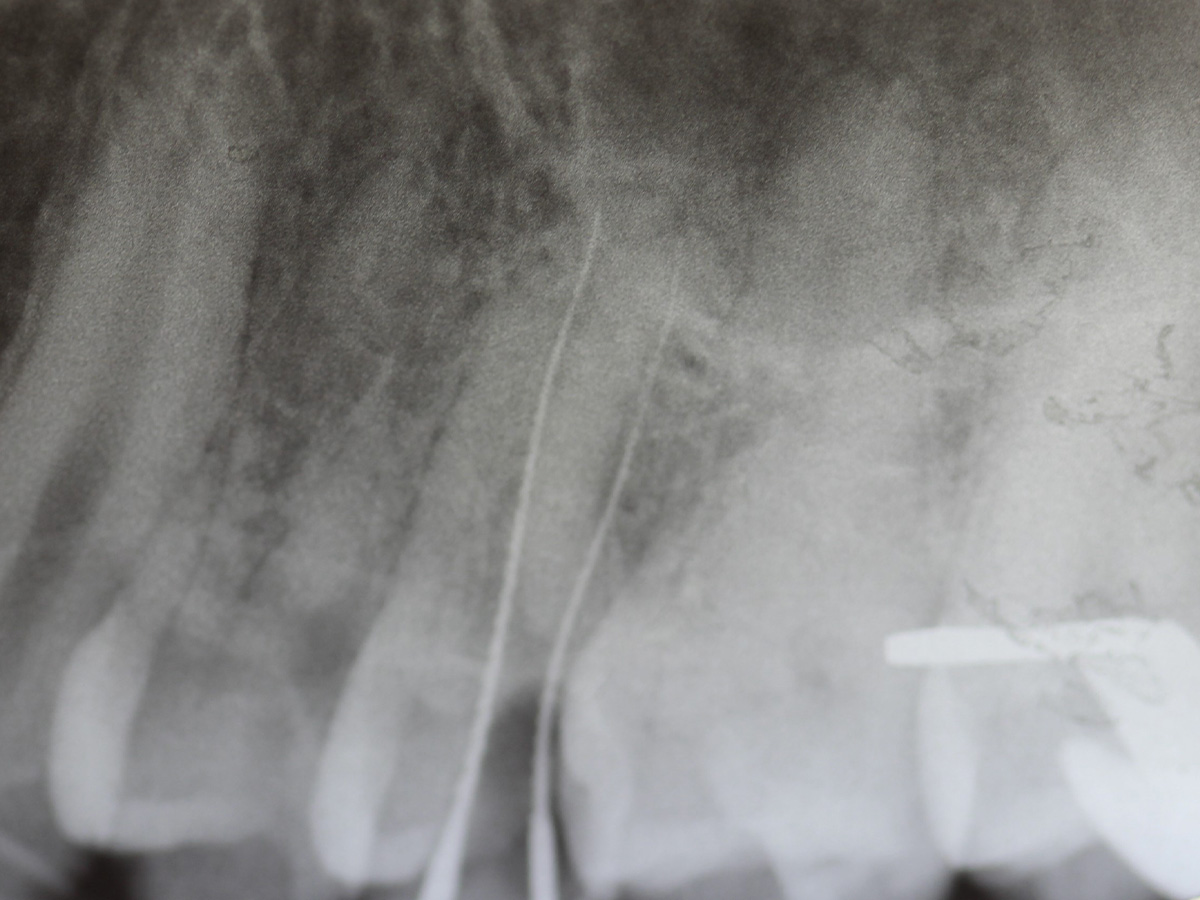

Abbildung 1

Bissflügelröntgenaufnahme, Approximalraumkaries an Zahn 25 distal